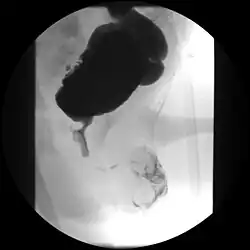

| A paraplegic patient with neurogenic bladder on regular ultrasound follow-up showing thickened bladder wall with trabeculations and sediments within the bladder. | |

Ultrasound imaging can give information on the shape of the bladder, post-void residual volume, and evidence of kidney damage such as kidney size, thickness or ureteral dilation.[12] Trabeculated bladder on ultrasound indicates high risk of developing urinary tract abnormalities such as hydronephrosis and stones.[13] A voiding cystourethrography study uses contrast dye to obtain images of the bladder both when it is full and after urination which can show changes in bladder shape consistent with neurogenic bladder.[12]